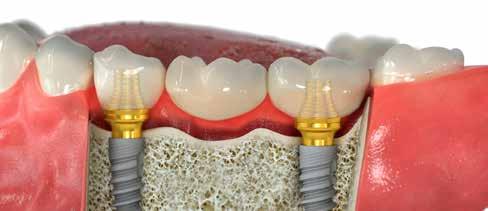

Az implantátumok hosszú távú sikerének egyik meghatározó eleme a megfelelő implantátumrendszer kiválasztása. A Straumann® BLT implantátumok, amelyeket szabadalmaztatott Roxolid® anyaguk és SLActive® felszínük jellemez, csontintegrációs potenciáljuk és stabilitásuk miatt kaptak kiemelt figyelmet.1,2 Ezek az implantátumok a természetes foggyökér formáját imitálják, apikális átmérőjük kisebb, mint a nyaki részen. Formai kialakításának bizonyított előnye, hogy rossz csontminőség esetén is növeli a primer stabilitást a kortikális csont kompresszióján keresztül, illetve csökkenti a csontperforáció veszélyét.3

Ez az esetismertetés két, az esztétikai zónában elhelyezett Straumann® BLT implantátum kilencéves utánkövetését mutatja be, vizsgálva a klinikai teljesítményt, a periimp-

lantáris szövetek egészségét és a páciens elégedettségét. Az élettartam és az esztétikai eredmények rávilágítanak, hogy a hosszú távú siker eléréséhez nélkülözhetetlen a gondos kezeléstervezés és kivitelezés.